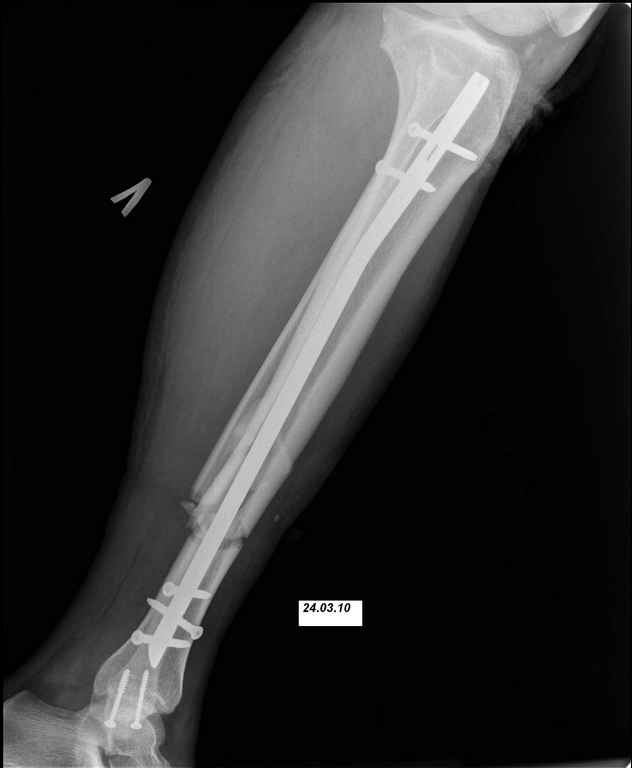

24.03.10 выполнены операции - БИОС перелома большеберцовой кости левой голени (штифт Synthes), остеосинтез перелома внутренней лодыжки левой голени винтами. Послеоперационный период протекал без осложнений. Выписан на 10 сутки. Амбулаторно не наблюдался.

Возможности и рассматриваемые варианты дальнейшего лечения: 1. удаление штифта, промывное дренирование, ЧКДО. Ждать сращения. 2. удаление штифта, ДРУ (по Челнокову А.Н.), понаблюдать несколько дней+антибиотики(в\в/в\м, перевязки), временно спейсер?, затем БИОС штифтом с АБ покрытием (есть штифты Synthes, Sanatmetal; по нашему мнению самый отпимальный вариант, НО более взрослые коллеги не поддерживает наших «новаторских» предложений, поэтому опыт штифтования с АБ покрытием небольшой). Варианты типа удалить штифт+гипс или вытяжение не рассматриваем. Подскажите, пожалуйста, какой вариант наиболее предпочтительней. И терзает вопрос, что привело к нагноению/остеомиелиту? Нестабильность? В настоящее время с пациентом проведена беседа, настроен на лечение, регулярное наблюдение, выполнение рекомендаций. Ждем Ваших советов и комментариев. Заранее спасибо.

Здесь в любом случае надо давно делать реостеосинтез, есть очевидная нестабильность. Поскольку пациент не сильно надежный, наверно, лучше бы сделать все в один этап. Удалить, дистрактором восстновить длину и ось, рассверлить мм до 14-15, помыть канал, и заштифтовать гвоздем с покрытием. Взять гвоздь длиннее этого. И для большей стабильности ввести винт(ы) мимо гвоздя.

Во первых штифт тонкий, во вторых коротккий. Не смотря на то что дистальное блокирование выполнено 3 винтами, связь с коротким дистальным отломком получиласть слабоватая если учесть активный образ жизни пациента и его "ненадежность" как выразился Александ Николаевич.